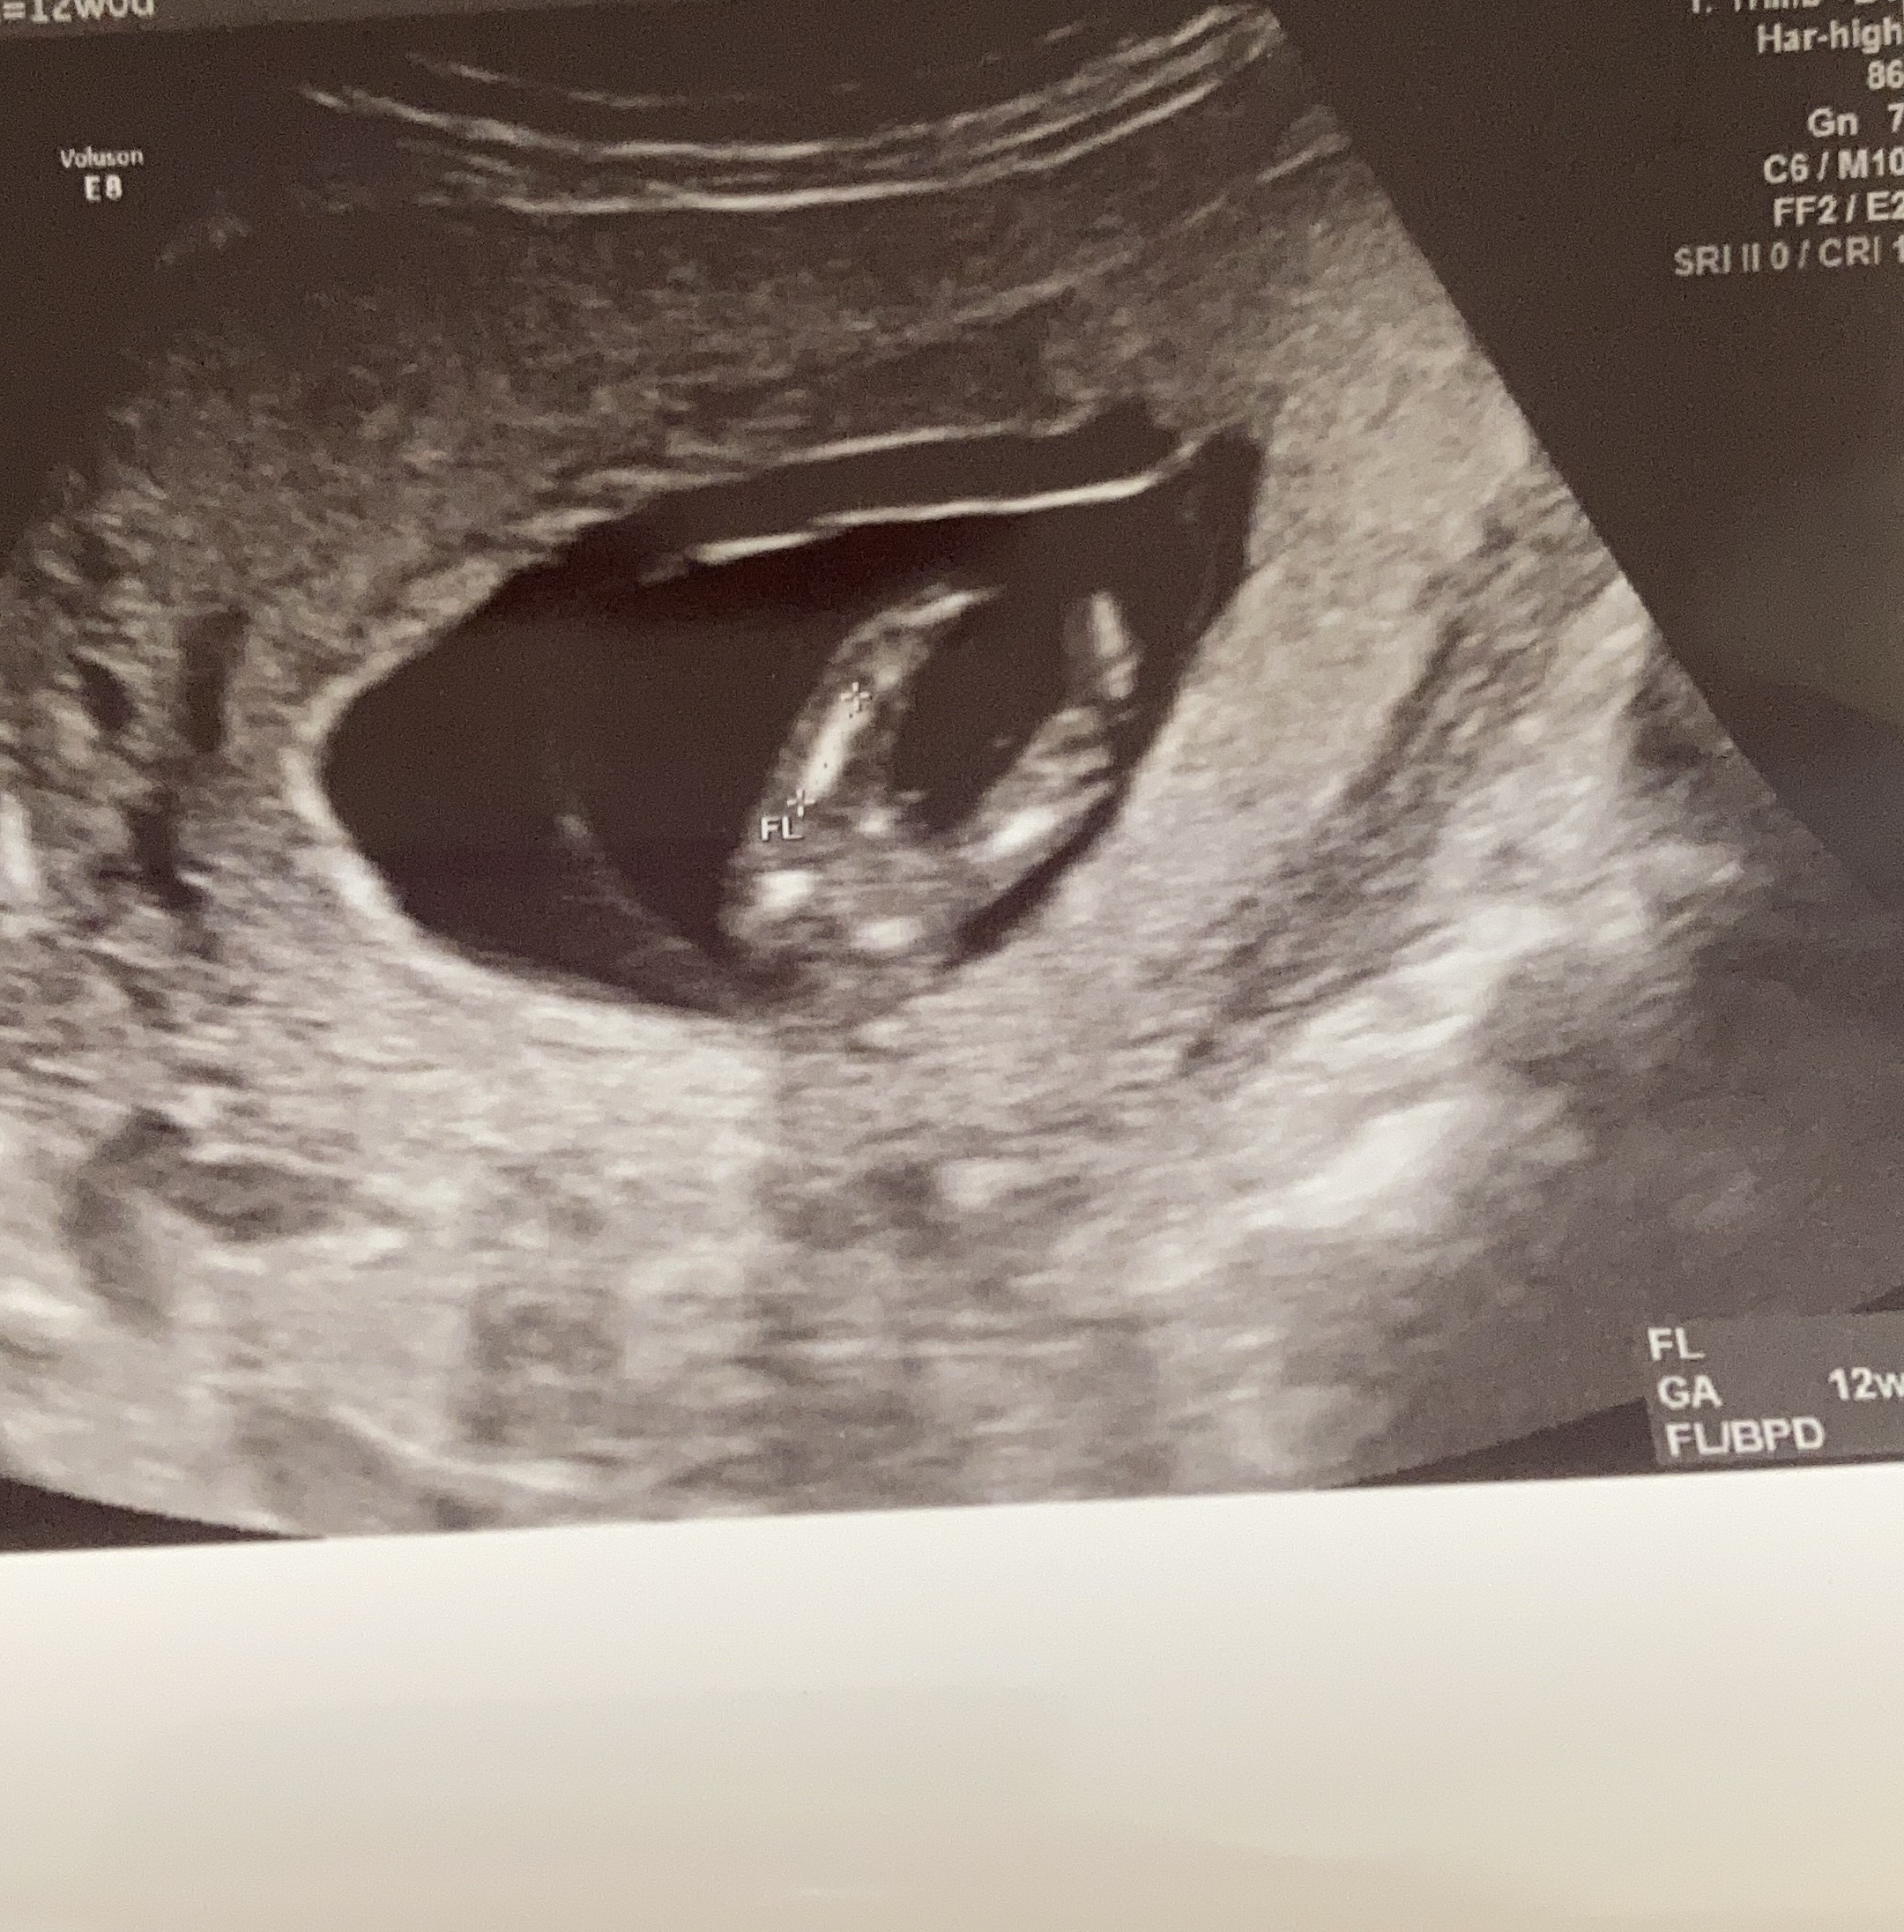

Za drugim razem uznałam, że przecież na niczym nie tracę, a szczęściu można trochę pomóc. Przerzuciłam się na nabiał, dużo mleka, kakao wieczorem orzechy, trochę słodkości. Całkowicie odrzuciłam banany, buraki i zredukowalam pomidory i ziemniaki... Pilnowałam także cyklu, mierząc poziom hormonów paskami owulacyjnymi praktycznie codziennie po okresie do momentu dwóch kresek... I udało się

będzie córka. Trzymam kciuki za powodzenie! Nie jest to na pewno 100% metoda, ale wierzę, że coś w niej jest.